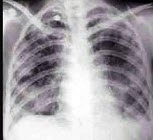

146、单项选择题

男,5岁。发热、胸痛、胸闷、气促。X线检查如图,最可能的诊断为()

A.右侧胸膜间皮瘤

B.右侧肺脓肿

C.右侧包裹性积液

D.右侧肺不张

E.右侧气胸